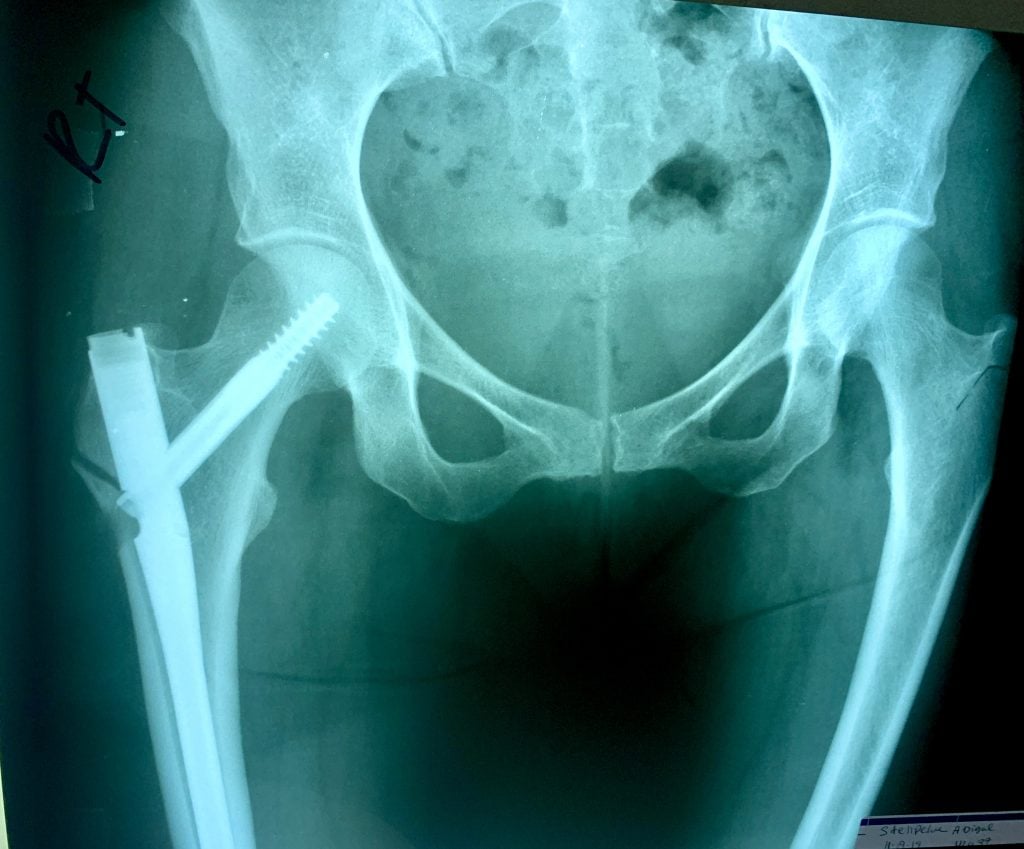

I started working with Dr. Goolsby and Dr. Serota in 2018 when I got a stress fracture in my left hip while training for the 2018 NYC Marathon. I was then diagnosed with osteoporosis and the injury took an abnormally long time to heal because of this. They got me running again and in 2019 I was PRing in every race that I did and had amazing training going into the 2019 NYC Marathon where I hopped to BQ. My dreams were cut way short when my right hip and femur spontaneously broke at Mile 14 of the race and I was taken off the course in an ambulance. I spent 5 days in a Queens hospital and have a metal rod in that right leg/hip. One of the first things I did in that ER on Sunday Nov 4, 2019 was reach out to Dr. Goolsby, who picked up on a Sunday, to seek her advice and start the wheels turning to come under her care because I trusted her completely. After months of rehab and working with Dr. Serota and Dr. Goolsby to improve my bone health, treat my RED syndrome, and heal my hip I was able to slowly resume running in the summer of 2020. After another setback in the spring of 2021, we determined my bones weren't yet ready to marathon. But after 3 long years and 3 days since I first was taken off the marathon course, I was able to complete the 2022 Marathon on Nov 6.